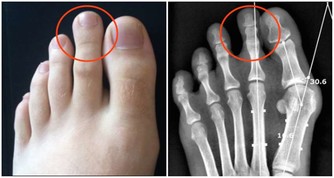

水喝得太少,會使尿中鈣和鹽的過飽度增加,形成晶體,引發腎結石。

Tips:如果尿尿顏色無色或微黃,那就表示你喝的水夠多了。